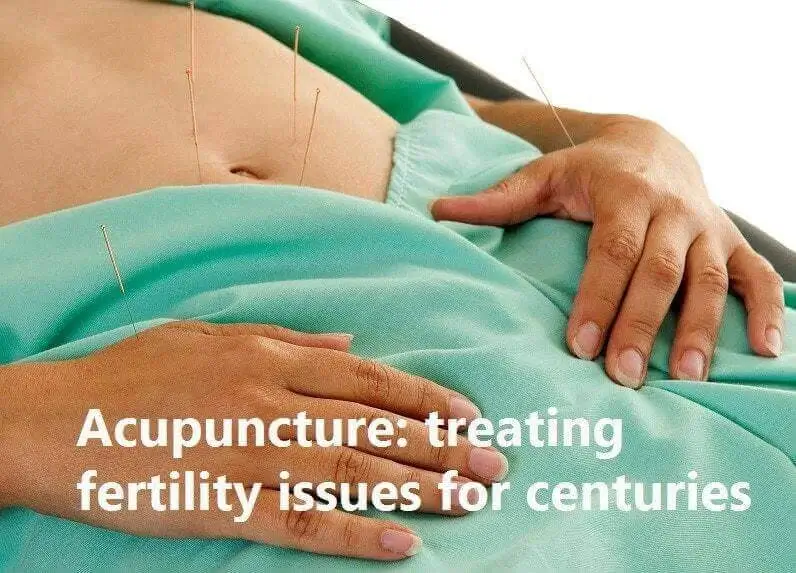

Georgetown Acupuncture at Natural Health Clinic of Halton (in the vicinity of the New Georgetown Trafalgar Memorial Hospital) are all professionally trained. We thoroughly assess each patient’s case and create a specific individualized wellness treatment plan to attain overall balance in the body. Georgetown Acupuncturists, (905) 582-2360 Acupuncture, an Ancient Treatment for a Current Problem. Acupuncture is known to treat a variety of conditions, s...

- Infertility • Georgetown • Acupuncture • Natural Health Clinic of Halton (February 14, 2017)